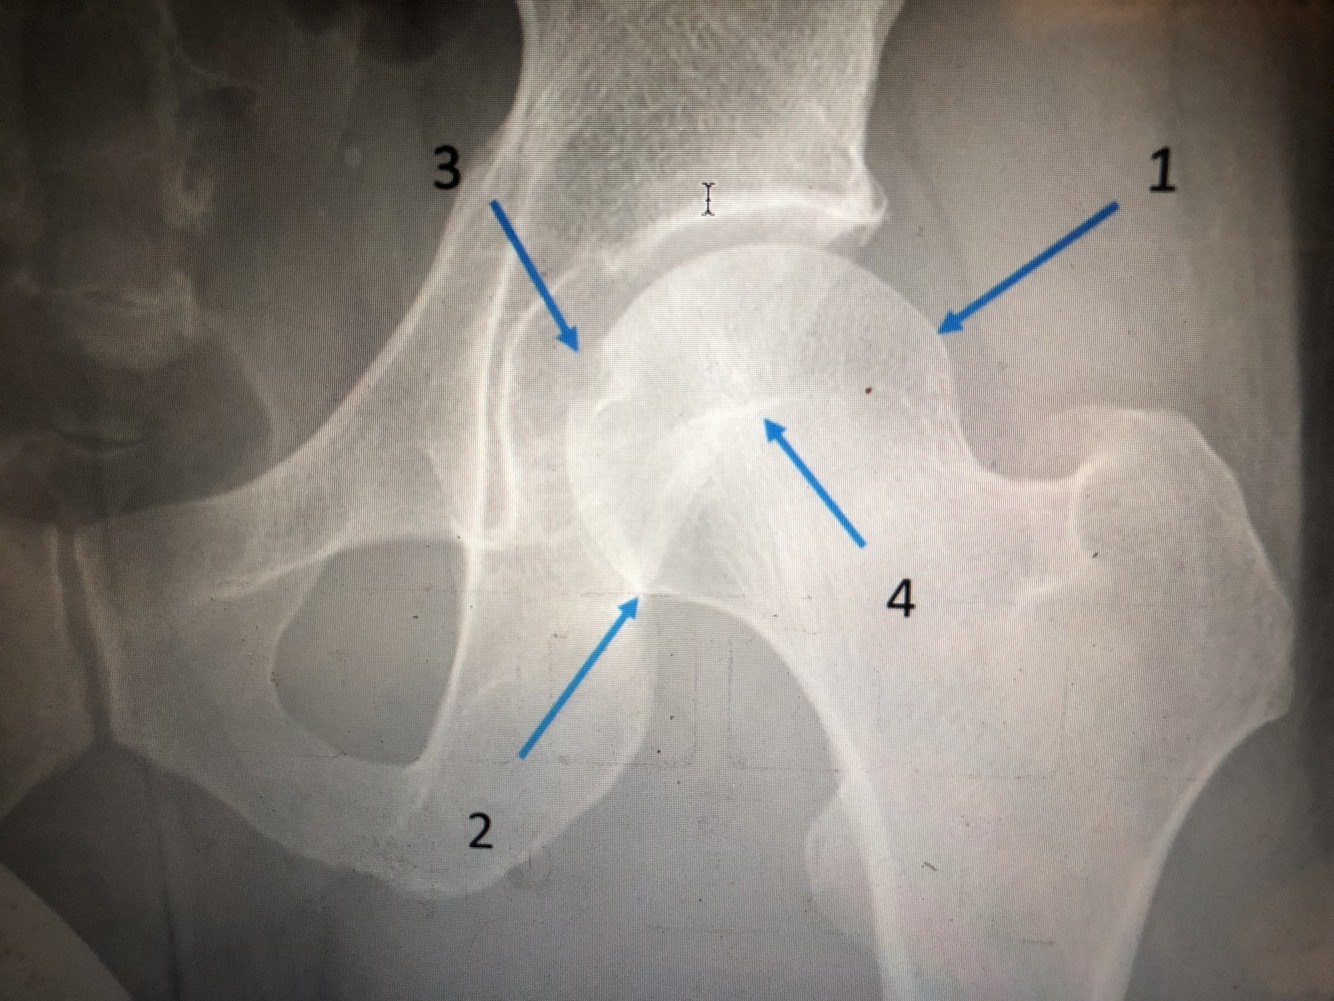

What is #1

lateral margin of femoral head

What is #2

medial margin of femoral head

What is #3

fovea centralis

What is #4

physeal line or scar